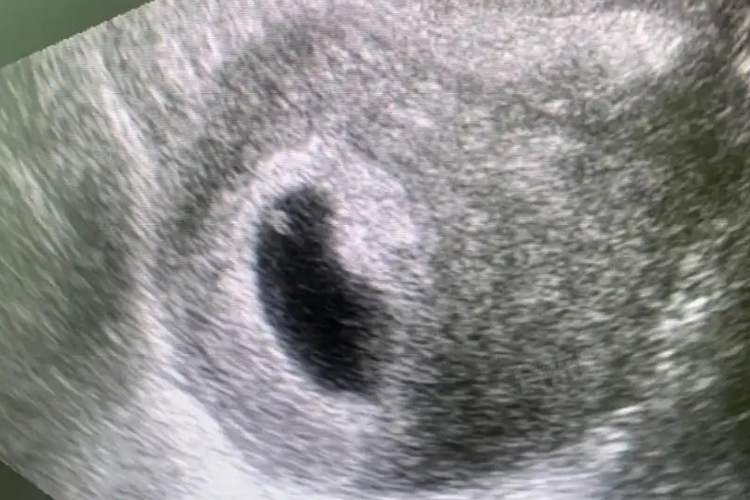

- 着床后,胚胎开始迅速发育,在怀孕5周左右,通过超声检查就有可能观察到卵黄囊。此时,卵黄囊通常表现为一个小的圆形或椭圆形无回声区,位于妊娠囊内,直径约2-5毫米。

1、判断胚胎发育情况:正常大小和形态的卵黄囊是胚胎健康发育的重要标志。若卵黄囊过大、过小或形态异常,如呈不规则形状,可能提示胚胎发育存在问题,如染色体异常、胚胎停育等。